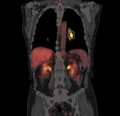

We are developing a Slicer command-line module for PET SUV computation and a wizard interface to a specific workflow for PET SUV computation for longitudinal studies.